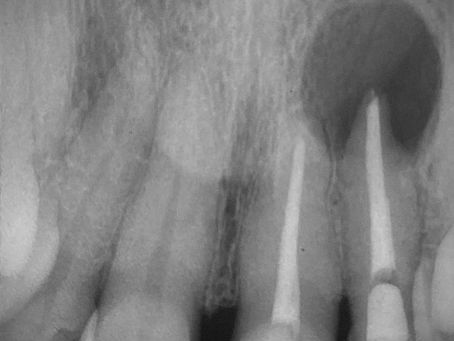

Casos clínicos

Explore nossos casos clínicos sobre o uso de cimento biocerâmico Cimmo: aplicações reais, abordagens práticas e resultados transformadores para inspirar e aprimorar sua prática odontológica.